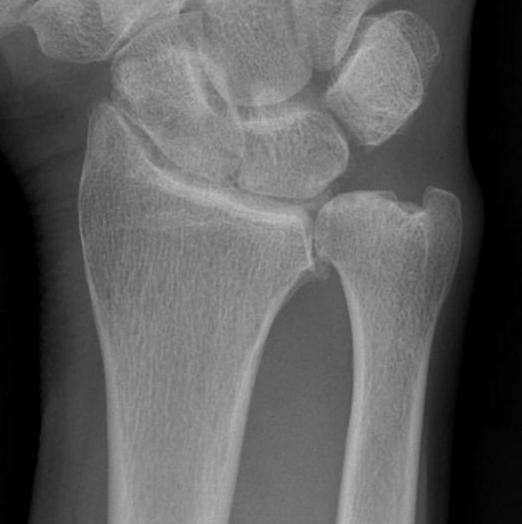

Bower's interpositional hemiarthoplasty

Technique

- best for young OA

- excision of arthritic portion through 5/6 compartment / hemiresection

- intact TFCC for interposition

Indications

- young OA

- not suitable in RA as TFCC damaged